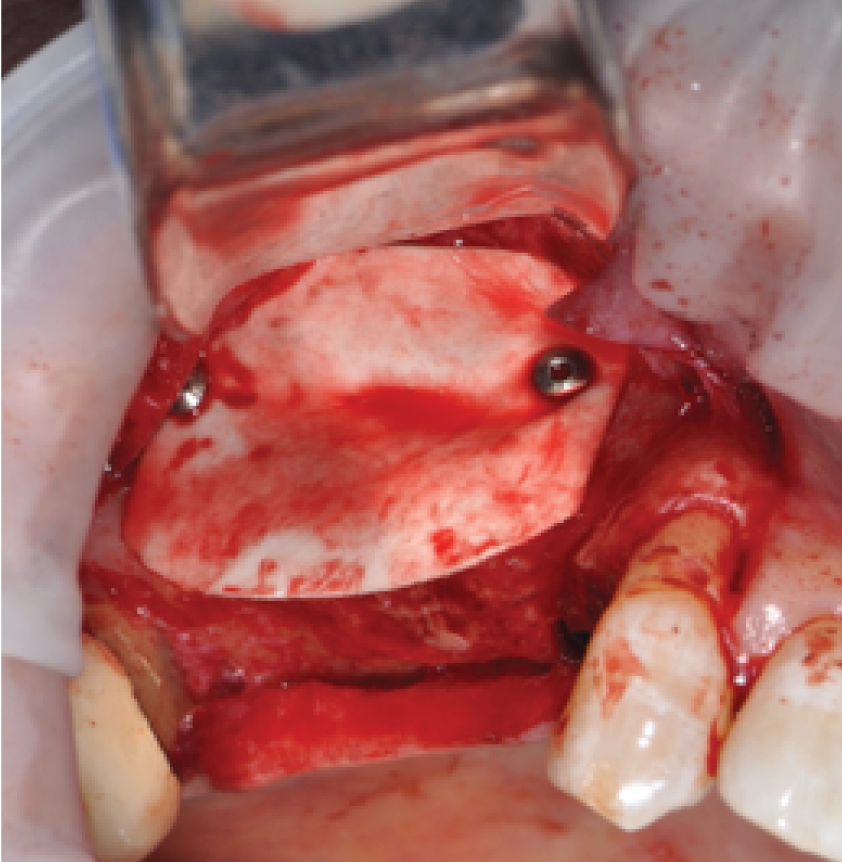

Director’s Clinical Cases

Director’s Clinical Cases